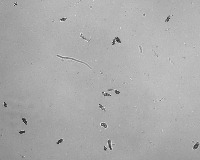

Spore-2022 Computer Vision Project

downloadsHere are a few use cases for this project:

-

Medical Research: "Spore-2022" can be used for identifying different types of spores in biological specimens under a microscope. This could provide pivotal data for advancements in medical research, particularly in diseases associated with spores.

-

Pharmaceutical Industry: The model can be used to inspect quality of antibiotics or other drugs derived from spore-forming organisms. It can identify and classify various spores, which can assist in maintaining the integrity and effectiveness of such products.

-

Agriculture: This model can be utilized for soil testing to identify and classify spores in the soil, thus helping farm optimizers in deciding which crops would be most profitable depending on the soil’s fungal biodiversity.

-

Environmental Science: Through continuous monitoring and identification of spore classes, the model can help in identifying changes in environmental conditions or the introduction of potentially invasive or harmful species.

-

Food Industry: "Spore-2022" can be used in the food processing and storage industry to ensure food safety by detecting and classifying harmful spores on food items or in storage environments that could lead to spoilage or present health risks.